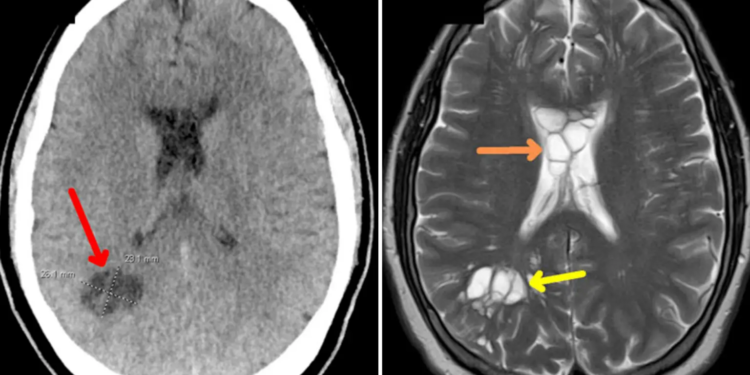

Στην συγκεκριμένη περίπτωση, ο ασθενής εκτός από το οίδημα, ανέπτυξε κύστεις και στις δύο πλευρές του εγκεφάλου του. Αργότερα, αυτό αποδείχθηκε ότι προκλήθηκε από τo παράσιτο (κεστοειδής σκώληκας) που είχε γεννήσει αυγά μέσα στον εγκέφαλο του άνδρα.